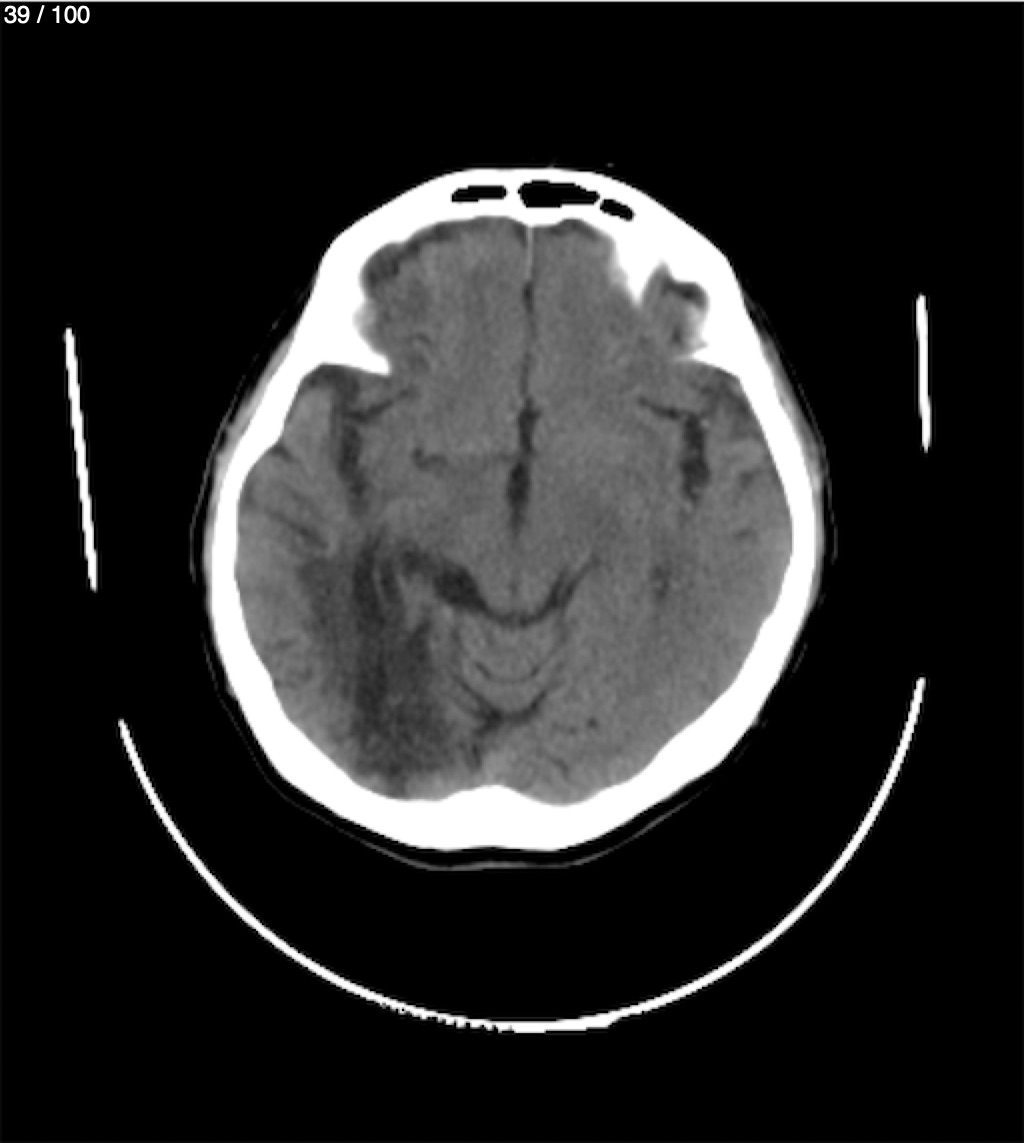

Catarino Perez Escobar 85A - T.C Craneo